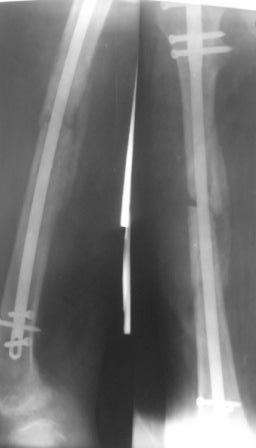

> лечения? Р-снимок прилагается.

Однако мозоль формируется.

Ждать...